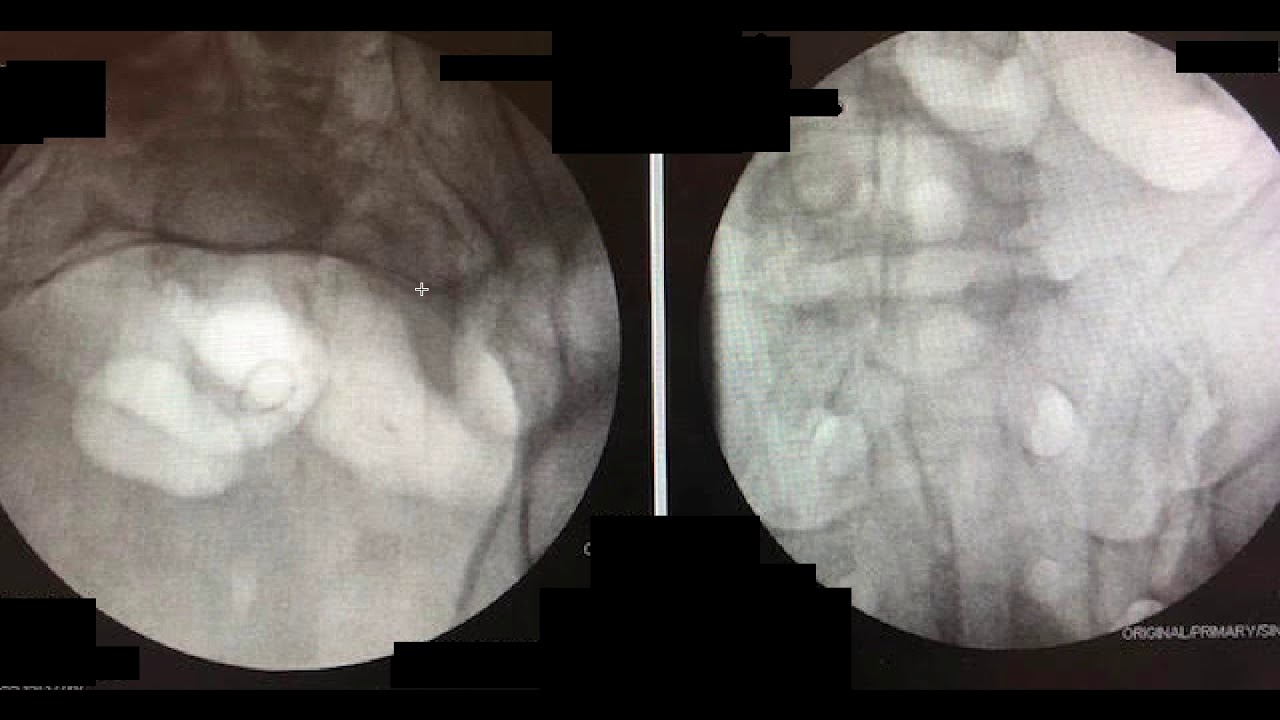

Dysmorphic Sacrum SI screw

Автор: Yelena Bogdan, MD - Orthopaedic Trauma

Описание: Description of tips and tricks for SI screw fixation in a dysmorphic sacrum. In case anyone wonders what technique I use for positioning and incisions, it is here: https://www.ncbi.nlm.nih.gov/pubmed/2...